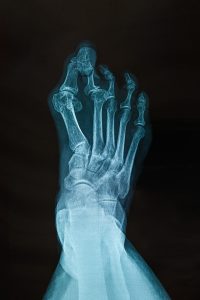

Plantar Fasciitis Treatment at York-Med Physiotherapy & Wellness Centre Plantar Fasciitis is a common and painful condition that involves inflammation of the plantar fascia, the thick band of tissue that